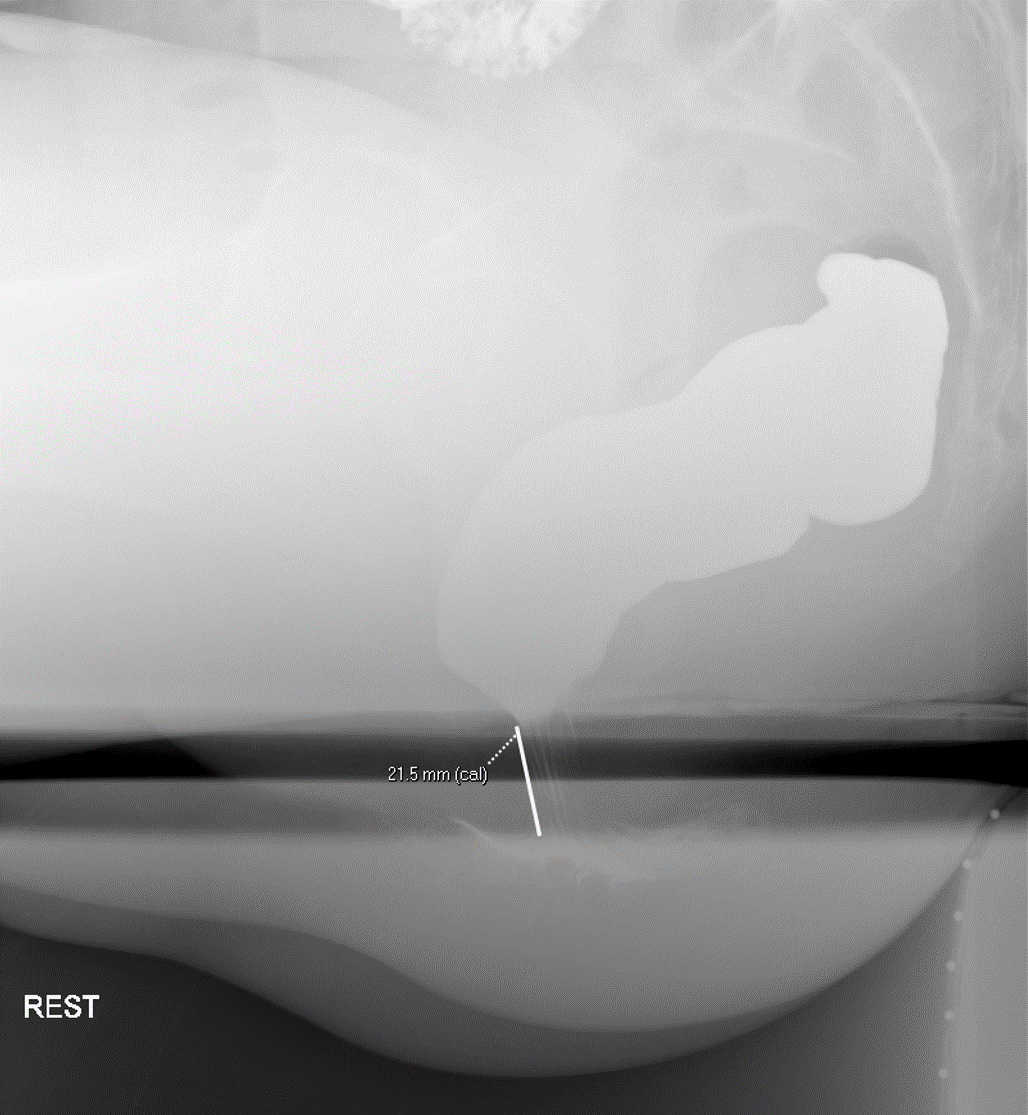

- Rest

(key image 2).

- Image interpretation:

- Anal Canal

- Width

- During evacuation, the width of the anal canal averages 15mm and seldom exceeds 2cm

(key image 4).

- Anal canal should remain closed in the resting state and with each maneuver other than defecation.

- Incontinence of barium/stool at any moment is abnormal.

- Length

- Measured as the distance between the external anal orifice and the point where the parallel straight sides of the anal canal meet the cone shaped walls of the distal rectum.

- The mean radiographic length of the anal canal is 22mm in men and 16mm in women

(key image 5).

- Anorectal junction position

- The anorectal junction is the point where the parallel straight sides of the anal canal convert to the diverging walls of the distal rectum

(key image 6).

- This point is measured in reference to the inferior margins of the ischial tuberosities.

- During maximal straining (defecation), the anorectal junction should descend no more than 3.5 cm from its resting position.